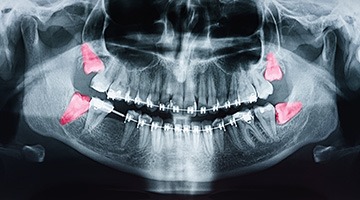

The wisdom tooth extraction procedure is surprisingly straightforward. After you’ve met with Dr. Branberg for your consultation, he’ll be able to determine if your wisdom teeth need to come out after inspecting your smile, taking X-rays, and discussing your symptoms with you. From there, a treatment plan is put together.

Partially erupted wisdom teeth can normally be loosened and then gently removed using specialized instruments; however, in the case of fully impacted wisdom teeth, a small oral surgery may be necessary. During this approach, the teeth are normally removed in sections to minimize the amount of bone loss and tissue disruption. In any case, our team will closely monitor you throughout the process and do everything we can to ensure your comfort and speedy recovery!

- Whether or not your wisdom teeth are impacted: Unfortunately, impacted wisdom teeth frequently require surgical intervention to remove. There are also two different types of impactions, bony impaction and soft-tissue impaction. Bony impaction requires the assistance of an oral surgeon to remove a tooth completely lodged in the jawbone, while soft tissue impaction is when your wisdom tooth is fully or partially emerged from the gums.